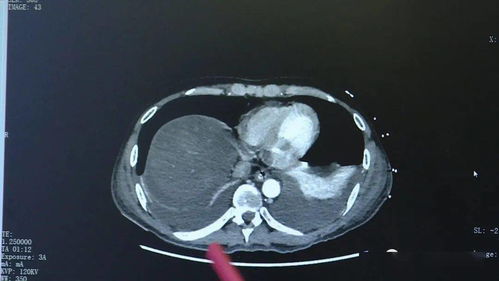

据报道,这名男子平时酷爱生吃腌制食品,尤其是生腌胆道类食物,在一次体检中,医生发现他的胆道内竟然有七条寄生虫,这一发现令医生感到十分惊讶,也引起了公众对生食安全性的关注。

在上述事件中,这名男子很可能是因为食用未经充分处理的生腌胆道类食物而感染了寄生虫,这些寄生虫在胆道内寄生并繁殖,导致胆道发炎、堵塞等问题,这不仅影响了男子的健康状况,还可能对他的生活造成严重影响。